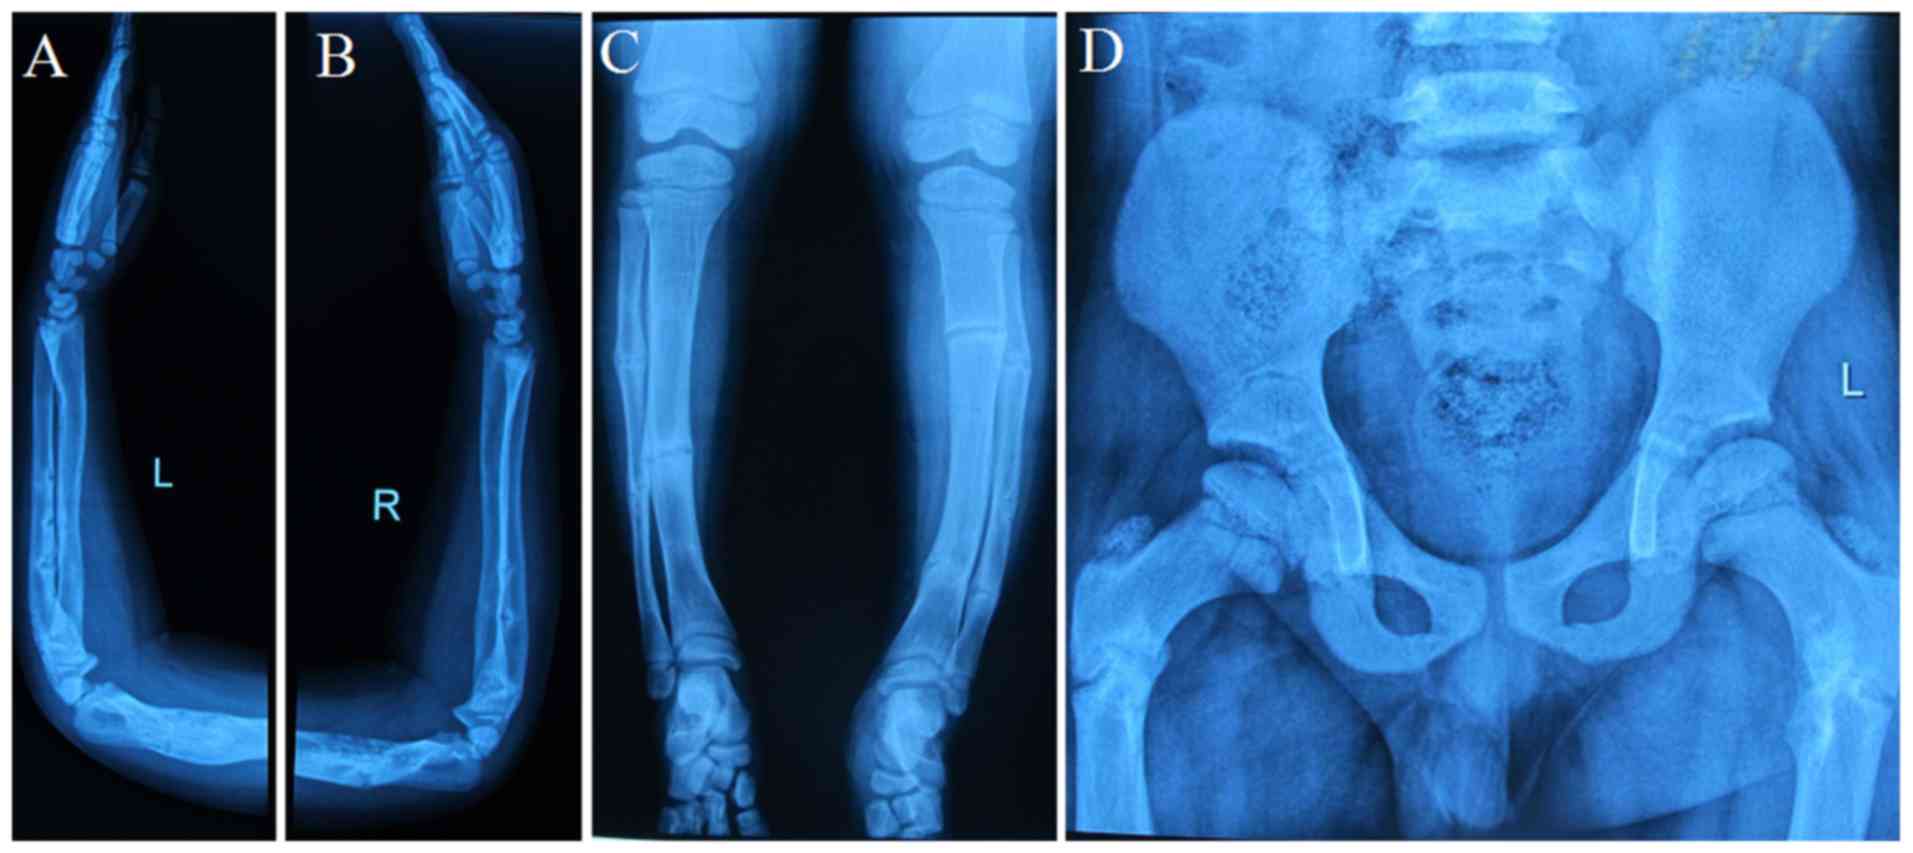

(Gly1012Ser), aĭefect compatible with OI type 2 as well as OI type 3. Gene, chromosome 7, exon 46 c.3034GC>A:p. Mutation with autosomal dominant inheritance in the COL1A2 Weĭecided to proceed with genetic testing for OI in order to haveĪ precise molecular diagnosis. Laboratory tests were all within normal limits. Malformations, some of which had been treated surgically (FigureġA and B). Radiographic investigation revealed severe

Revealed severe malformations, some of which had been treatedīone mass density (L1-L4) was measured 0.62 g/cm 3 withĪ Z-score of -3.8. The patient was mobilizing both withĪ cane and a wheelchair alternatively. (OI), type 3 (progressively deforming OI). This point, she was treated based on the clinical manifestationsĪccording to Sillence classification of Osteogenesis Imperfecta Sociology and a current student at the Art School of Acting. Hip) as well as severe scoliosis, poor hearing, blue sclera, andĭentinogenesis imperfecta. She reported a history of multiple spontaneous skeletalįractures since the 8th day of birth (humoral, rib, femoral and A 36-year-old woman sought consultation for low boneĭensity.